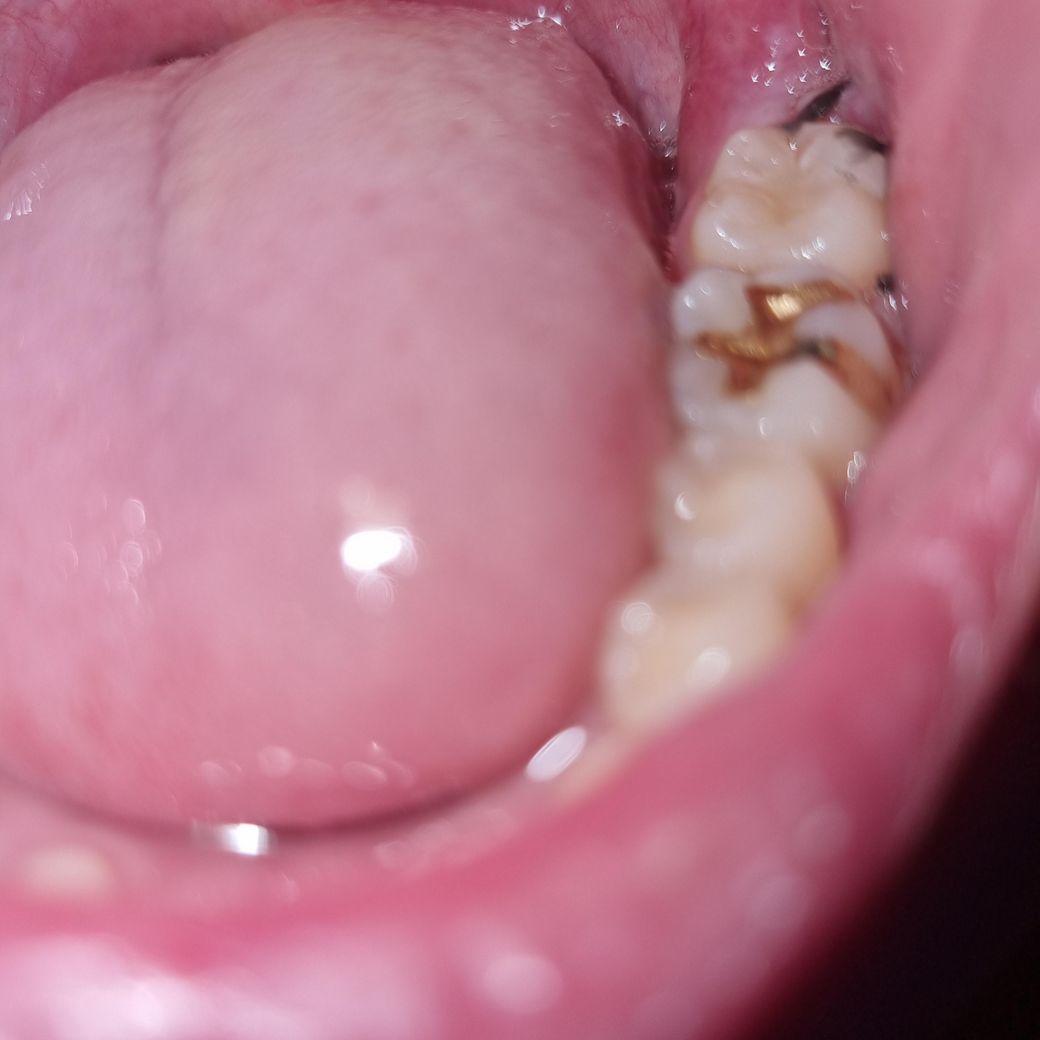

일주일 전에 위아래 어금니 충치를 레진으로 치료했는데 어제 양치하다가 아래 어금니에 붙은 노란게 떨어졌어요. 이게 레진인지는 정확히 모르겠고 뭔가 묘하게 그 부위가 파인 것 같기도 한데... 저는 확실히는 모르겠고ㅜㅜ 일단 어금니끼리 맞물릴때 아래 어금니에 통증이 있는데 치과에 가서 확인해달라고 해야하나요? 위에 어금니는 아프지 않습니다

사진은 화질은 안 좋지만 혹시 몰라서 첨부해봅니다..

사진에서는 통증의 원인이 될 만한 것은 보이지 않지만 교합 이상 등이 있을 수 있으니 통증이 있으면 치과 가보셔야 합니다.

레진은 쉽게 떨어지진 않습니다 . 사랑니 발치를 하신거 같은데 사랑니 발치한 곳의 음식물이 아닐까 생각됩니다.

사진이 흐려 정확히 보이진 않으나 레진이 탈락하진 않은 것 같습니다. 노란 건 아마 이물질, 치석이 아닐까 싶습니다. 레진 치료 후에는 1주 정도 약간 통증, 시림 등이 있을 순 있습니다.